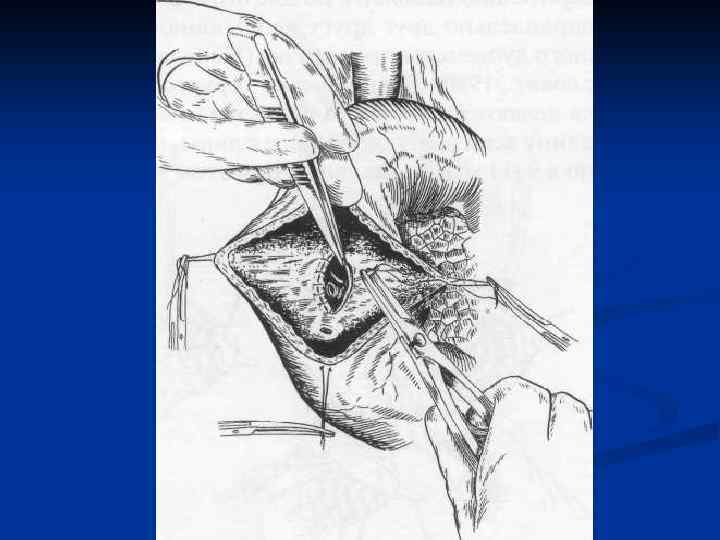

I. Восстановительные операции (восстановление проходимости протоков) 1. Эндобилиарные вмешательства под УЗИ или R – контролем (бужирование, баллонная дилатация, стентирование протоков). 2. Пластика стриктуры 3. Иссечение стриктуры с наложением анастомоза. II. Реконструктивные операции (наложение билиодигестивных анастомозов) 1. Анастомозы внепеченочных желчных протоков: а) с двенадцатиперстной кишкой (ХДА) б) с тощей кишкой (гепатико-, холедохоеюноанастомозы по Ру или по Брауну). 2. Анастомозы внутрипеченочных желчных протоков с сегментом тощей кишки, выключенной по Ру или желудком при высоких стриктурах

I. Восстановительные операции (восстановление проходимости протоков) 1. Эндобилиарные вмешательства под УЗИ или R – контролем (бужирование, баллонная дилатация, стентирование протоков). 2. Пластика стриктуры 3. Иссечение стриктуры с наложением анастомоза. II. Реконструктивные операции (наложение билиодигестивных анастомозов) 1. Анастомозы внепеченочных желчных протоков: а) с двенадцатиперстной кишкой (ХДА) б) с тощей кишкой (гепатико-, холедохоеюноанастомозы по Ру или по Брауну). 2. Анастомозы внутрипеченочных желчных протоков с сегментом тощей кишки, выключенной по Ру или желудком при высоких стриктурах